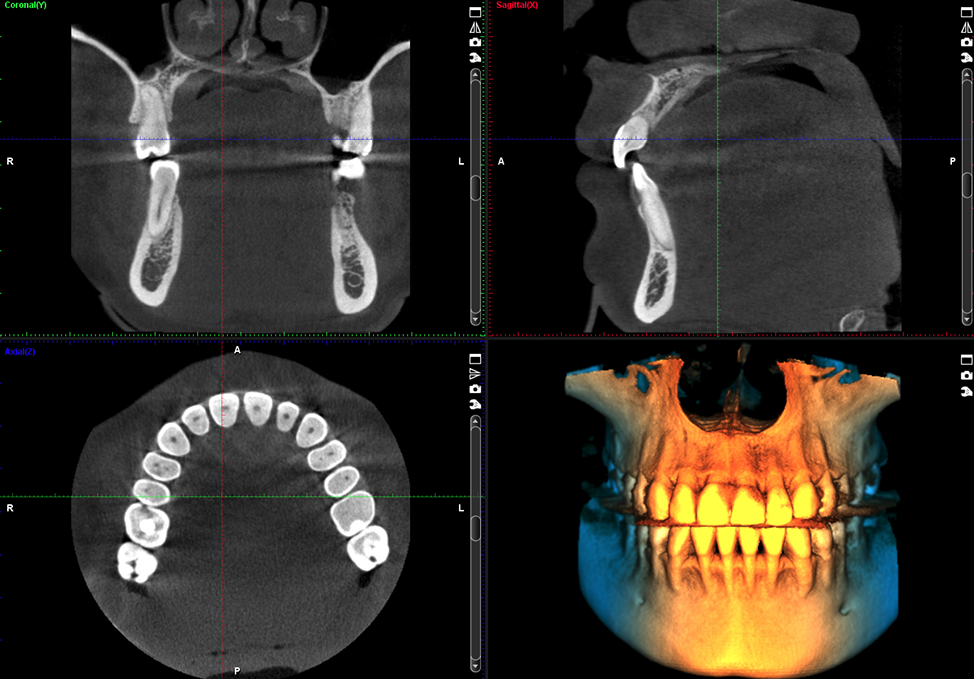

Canino impactado

Volumen 8 x 8